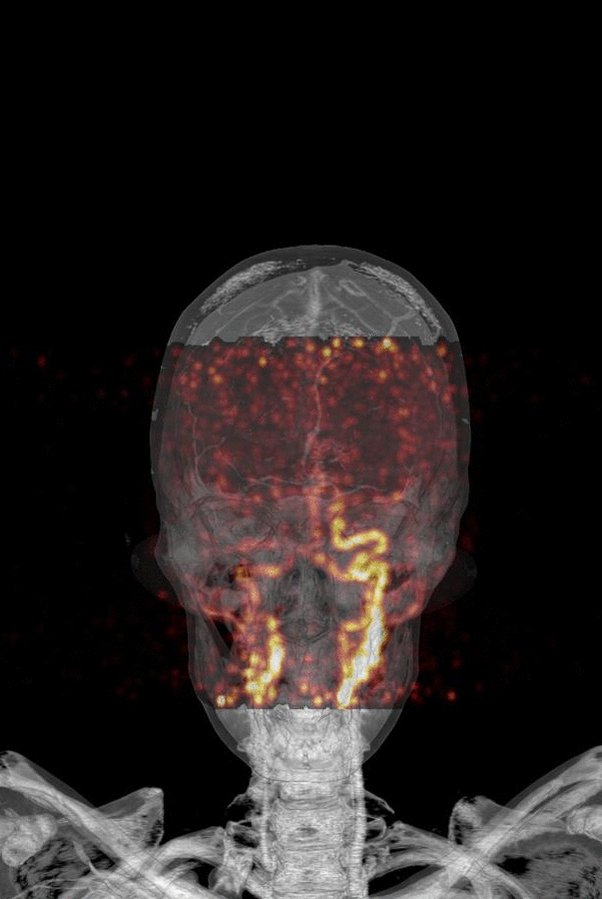

32yr old patient with stenosis of the right arteria carotis interna - PET for exclusion of large vessel vasculitis. We did a dynamic (list mode) PET to visualize the vessels. (1/2) #dynamicPET #MolecularImaging #radiology #FOAMrad #radres